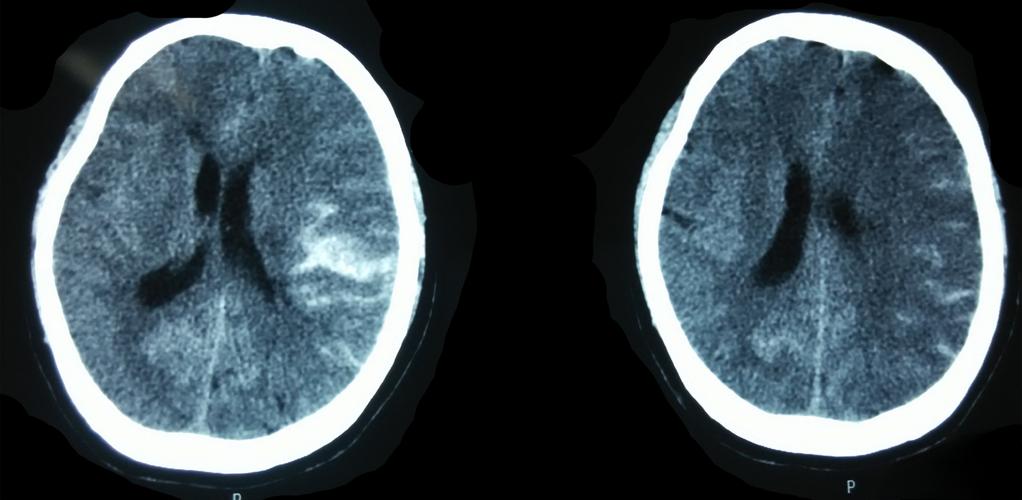

在新生儿,尤其是早产儿中,SAH 是一种常见的颅内出血类型,它通常是由于在分娩过程中,特别是顺产时,胎儿头部受到产道的挤压,导致脆弱的脑血管(主要是静脉)撕裂出血,血液积聚在脑表面的蛛网膜下腔。

好消息是,绝大多数(约90%)的SAH属于轻度(I-II级),出血量少,通常不会造成严重的脑损伤,预后良好,可能不会留下任何明显的后遗症。

当出血量较大(III-IV级),或合并了其他类型的颅内出血(如脑室内出血、脑实质出血),或者新生儿本身存在其他高危因素(如早产、低出生体重、缺氧等)时,就可能出现以下一种或多种后遗症: